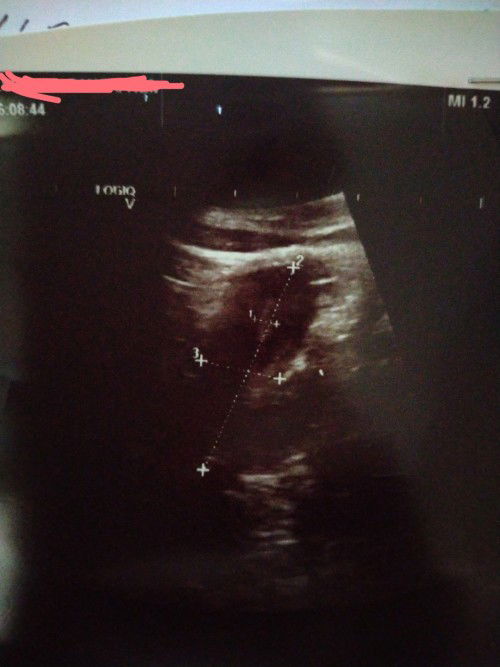

Last period sy buln 8.2022..tp hnya drh coklat2 je..bukn drh period..buln 9 sy cek upt tiga hri beturut..naik double line..lpstu sy biar dlm smnggu bila cek jd negatif semula..sy igt dh x,ada rzki la..lpstu skrg ni dh 4 buln sy x dtg priod..ada la slalu sakit2 bwah perut mcm nk priod..tp bila tggu x priod smpai ke hri ni..sy ada prgi checkup doc buln 1.2023 td..upt dgn drh beta hcg mmg negatif..bila scan dpt mcm bwah ni..doc x bgthu apa pun ttg scan ni..doc cuma refer kes sy dkt pakar nti..sy jd mkin kliru..x tau apa situasi sy skrg ni..